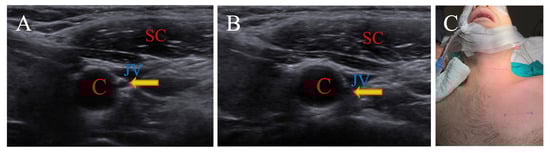

3.1.1. Contralateral Head Rotation for Nervus Vagus

| SCM | Sternocleidomastoid |

| C | Carotid artery |

| JV | Jugular vein |